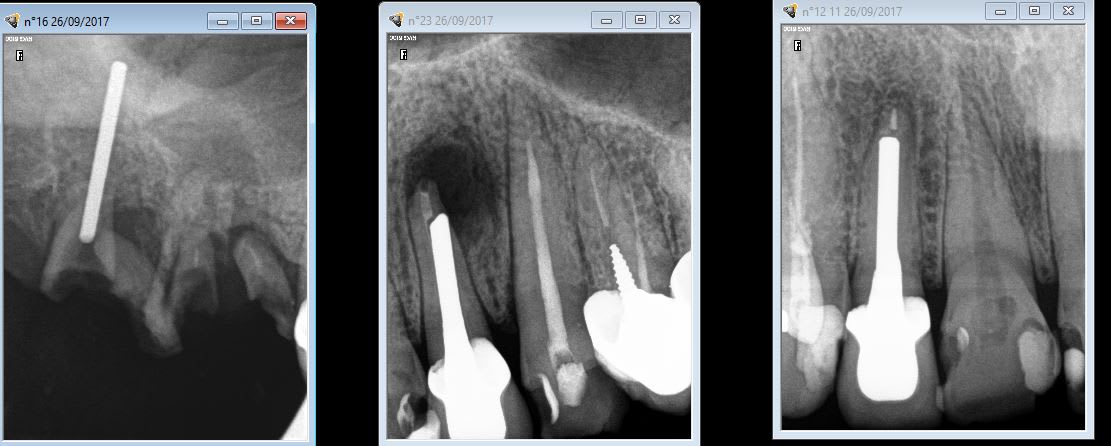

Je ne vais pas participer au concours "tenon de travers", j'en ai de jolis mais leodagan a mis la barre assez haute. Je vous propose plutôt le choix du format du tenon à la place. C'est qui qui a la plus grosse?

Si j'en crois le praticien qui a posé, les deux mon général!